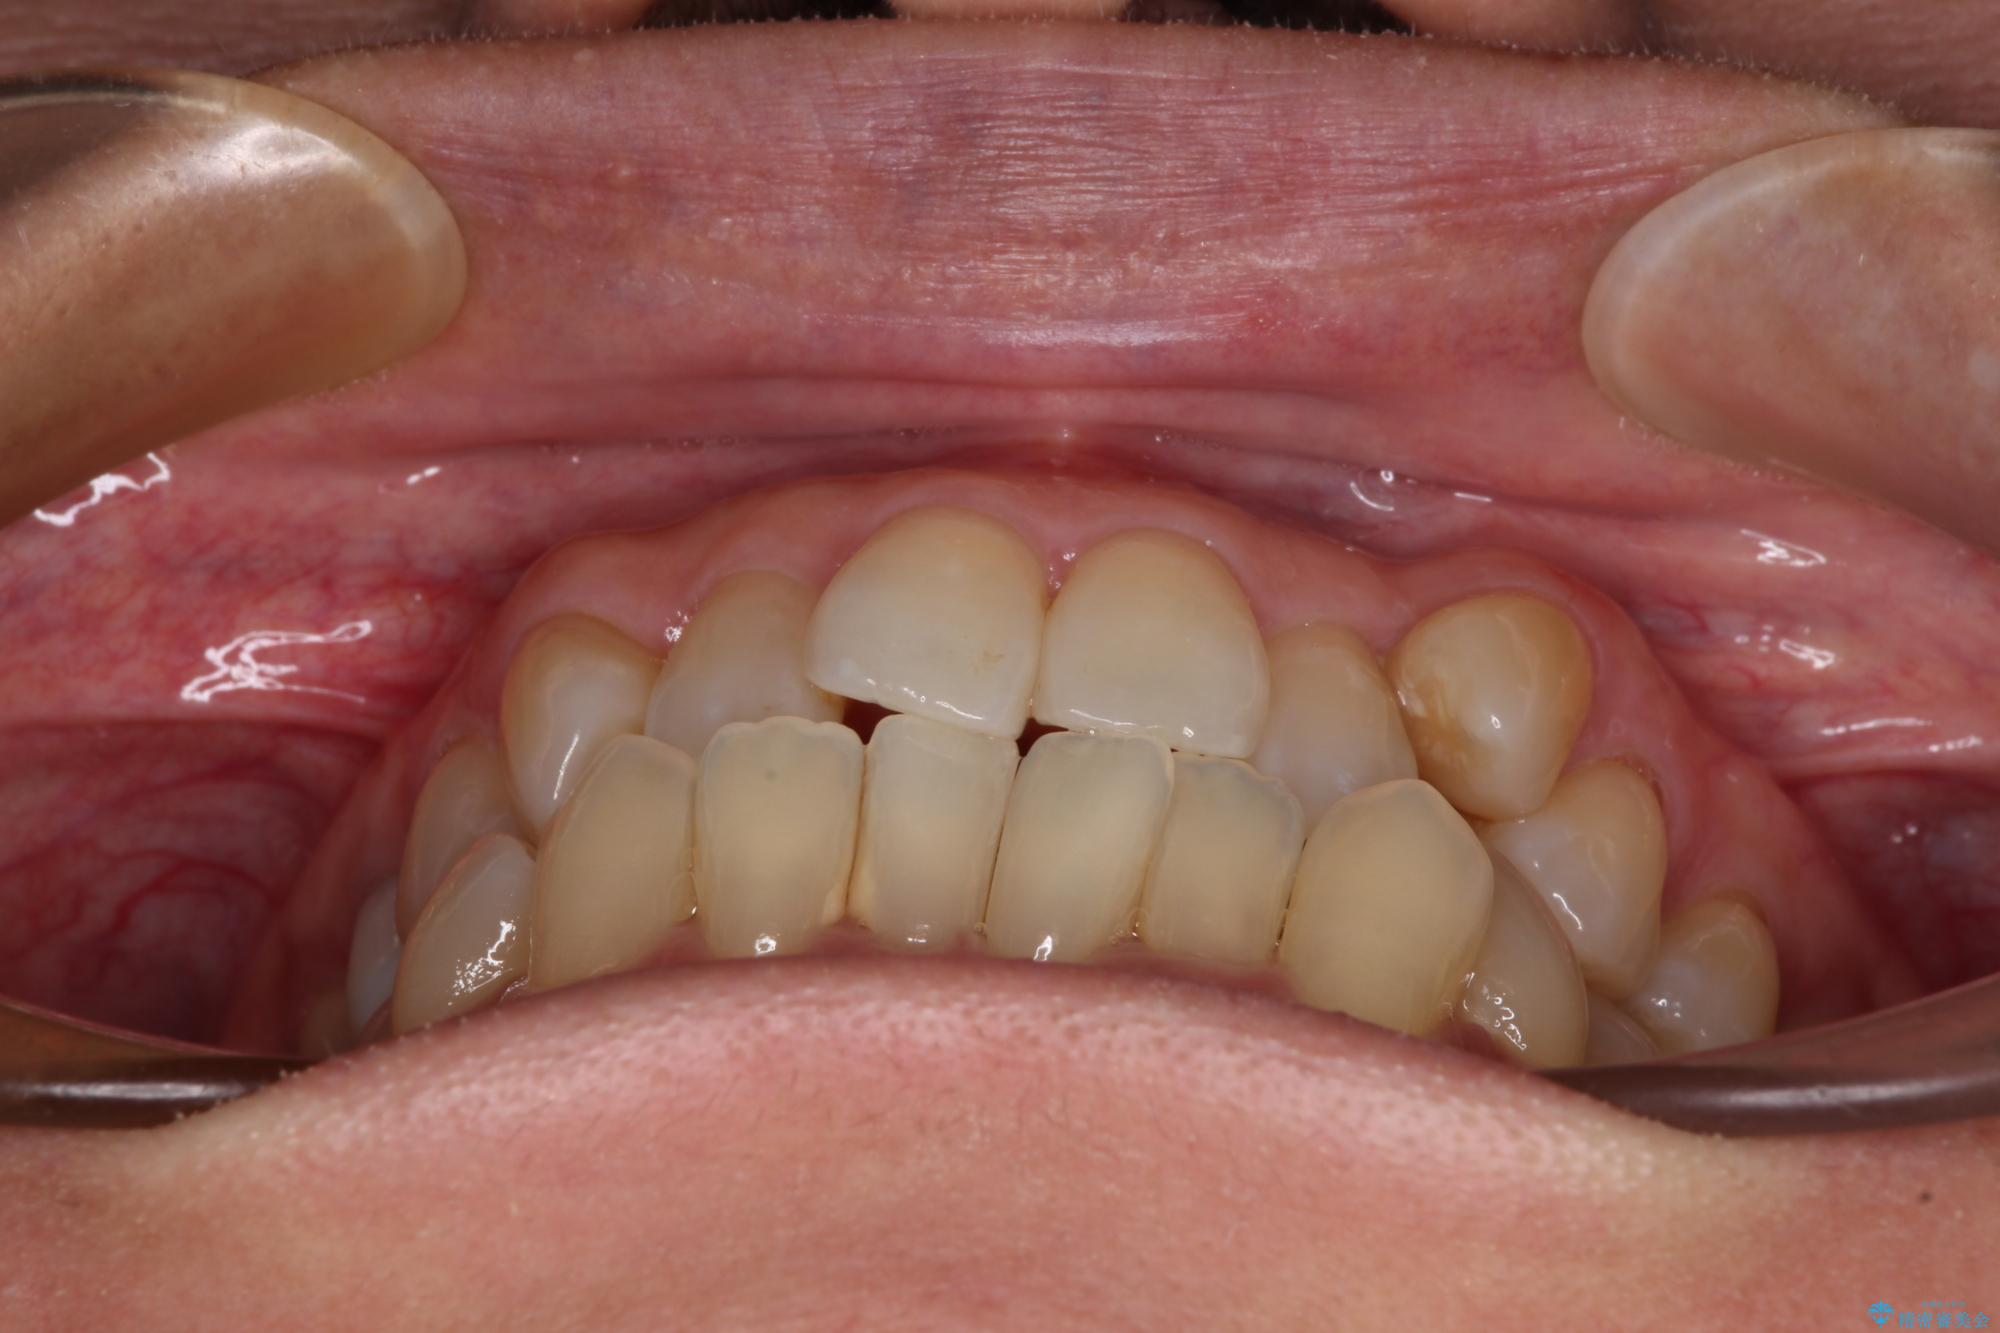

受け口と八重歯を改善 インビザライン矯正治療

- 前歯のデコボコや八重歯を治したいとのことで来院された患者様です。

受け口傾向の骨格であり、前歯はクロスバイトまたは切端咬合となっており、下顎を中心に歯列全体の後方移動を行い、IPR(歯と歯の間を削る)によってデコボコが解消するように設計し、インビザラインにより治療を行うこととしました。

受け口傾向のインビザライン矯正は比較的治療を行いやすいため、きれいに仕上げることができました。舌の突出癖が顕著であったため、改善のためのトレーニングをしっかりと行っていただきました。